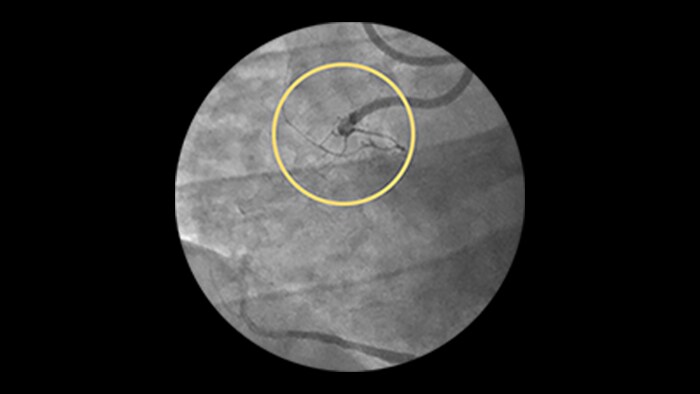

Calcified Lesions

Advanced tools for optimal PCI outcomes

2. Ambrosini, V, et.al. Early outcomes of high energy laser (Excimer) facilitated coronary angioplasty on hard and complex calcified and balloon resistant coronary lesions: LEONARDO Study. Card. Revasc. Med 2015: 16: 141-146 and Luc Bilodeau, MD, et al. Novel Use of a High-Energy Excimer Laser Catheter for Calcified and Complex Coronary Artery Lesions. Catheterization and Cardiovascular Interventions (62:155-161, 2004).